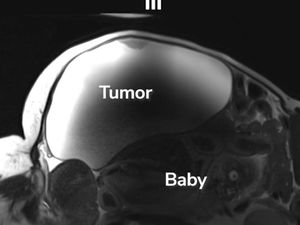

Langka! Ibu Ini Lahirkan Bayi dari Kehamilan di Luar Rahim dengan Kista Hampir 10 Kg

Seorang ibu di AS tak menyadari dirinya hamil karena janin tumbuh di luar rahim. Ia juga memiliki kista ovarium hampir 10 kg. Begini kisahnya.